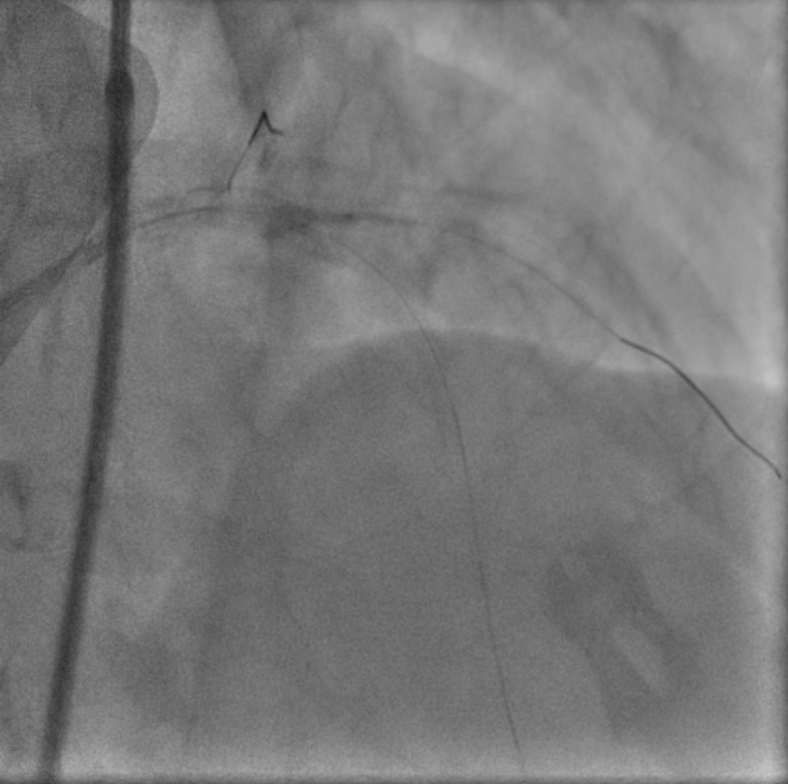

As patient is having cardiogenic shock from a LM occlusion and refusal of CABG, a high-risk, mechanically-supported PCI was undertaken. An IABP was inserted via the left femoral artery for hemodynamic support.Right femoral artery approach. 7Fr EBU 3.5 Guide. LAD and LCx were wired with microcatheter support. 2.0 balloon was used to predilate the LM-LAD lesion, TIMI 3 flow restored.IVUS was performed, showing heavily calcified plaque throughout the LM and LAD. Based on IVUS sizing (LM: 4.5mm, pLAD: 4.0mm), predilation with NC balloons followed by Intravascular Lithotripsy (IVL) with a 3.0 Shockwave balloon for 70 cycles were performed.A 2.75/40mm DES was placed in the mid-LAD and a 3.5/24mm DES was deployed from the ostial LM into the proximal LAD. POT in the LM using a 4.5 NC balloon, followed by post-dilation of the proximal LAD with a 4.0 NC balloon.Post-angiography revealed a jailed D1 with TIMI 0 flow. Rewiring to D1 was reattempted successfully with a CTO wire. Switched back to workhorse wire, dotted and predilated with 1.5 semi-compliant balloon. However IVUS showed wire likely true-false-true with ostial D1 in subintimal. Decided not to further intervene on D1.Final IVUS showed satisfactory results. Angiogram after adenosine showed regained flow in D1, TIMI 3 flow in both LAD and D1. Patient remained hemodynamically stable on IABP support post-procedure.

Case Summary